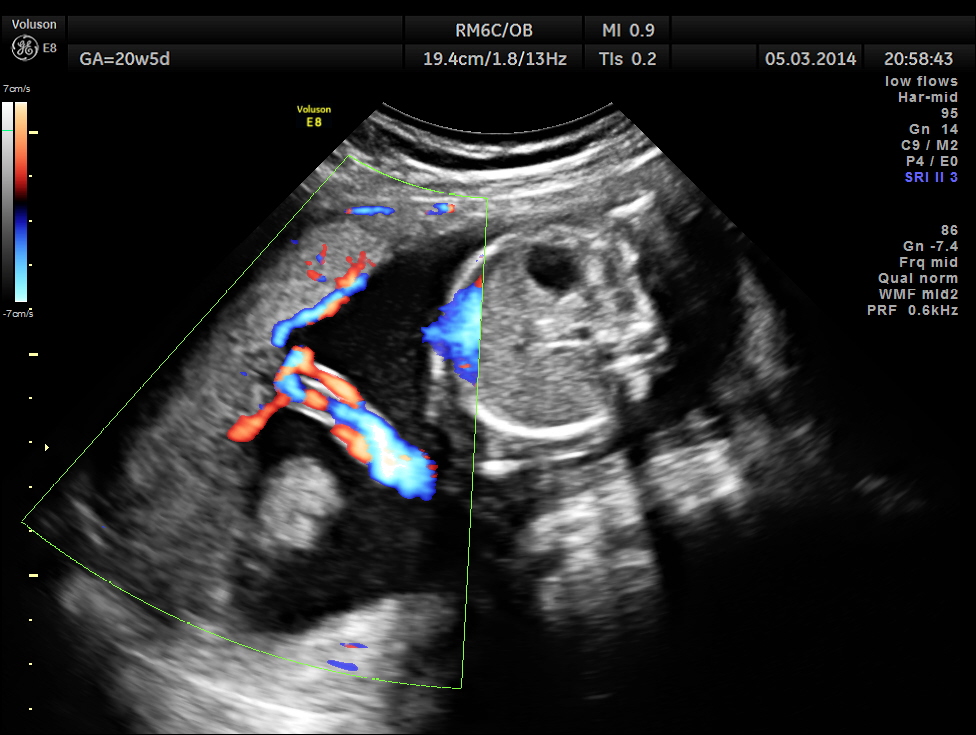

The placenta was on the anterior wall and the scan showed a distinct mass lesion in the antero right lateral portion. The placenta had multiple small cystic appearance in the right lateral aspect . Colour doppler showed no increased vascularity.

Cord insertion seems to be at the junction of the normal and abnormal regions.